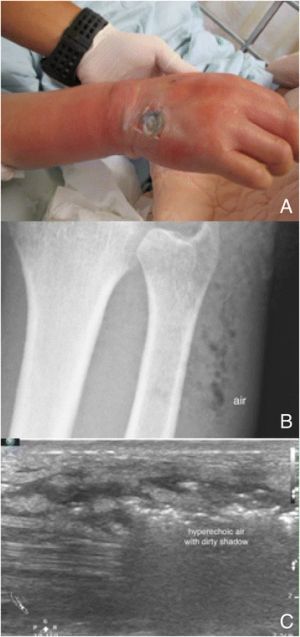

현장 초음파 검사(POCUS)는 MRI와 CT를 사용할 수 없을 때 괴사성 근막염 진단에 유용할 수 있다.[18] 심부 정맥 혈전증 (DVT), 표재성 농양, 정맥 울혈 등 괴사성 근막염의 초기 단계를 모방하는 질환을 구별하는 데도 도움이 된다.[18] 선형 프로브는 특히 팔다리 평가에 선호된다.[18]

괴사성 근막염의 특징적인 초음파 소견은 피하 조직의 비정상적인 비후, 공기, 체액이 있다는 것이다.[18] 이는 "STAFF"(Subcutaneous irregularity or Thickening, Air, and Fascial Fluid, 피하 불규칙성 또는 비후, 공기 및 근막 체액)로 요약할 수 있다.[18] 초음파를 사용한 괴사성 근막염의 공식적인 진단은 "광범위한 피하 비후와 2mm 이상의 근막 체액이 모두 존재하는 것"을 필요로 한다.[18] 피하 조직의 가스는 "불규칙한 음향 음영"을 나타낼 수 있다.[15] 그러나 다른 영상 기법과 마찬가지로 피하 유리 공기가 없는 것은 괴사성 근막염을 확정적으로 배제하지 않는다. 이는 질병 과정의 후반부에 나타나는 소견이기 때문이다.[18]